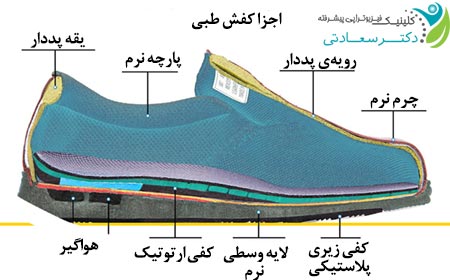

کفش مناسب بپوشید

کفش باید تمام قسمتهای پا بهخصوص کف پا را حمایت کند. این موضوع زمانی بیشتر اهمیت پیدا میکند که شما زمان زیادی روی پاهای خود میایستید یا بیش از حد از آنها استفاده میکنید، یا اینکه چاق هستید، باردار هستید، و یا اگر در فعالیتهای ورزشی شرکت میکنید.

ارتزها

ارتز سفارشی پا یک برجستگی در قوس عرضی دارد به صورتی که فرد هنگام راه رفتن احساس میکند یک ریگ در کفش گذاشتهشده است. این ارتز برای اصلاح مشکلات پای بیمار و کاهش درد کف پا ساختهشده است.